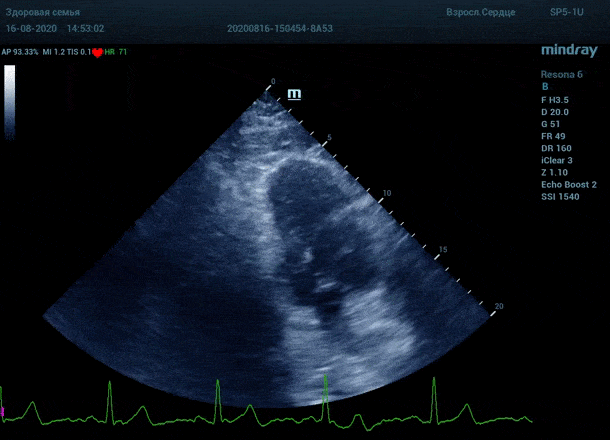

"Трудные пациенты" в эхокардиографии - явление не редкое. Часто встречается деформация грудной клетки или же площадь поверхности тела очень большая. Проблема акустического окна решается сменой положения тела пациента, снижением частот, изменением динамического диапазона и применением уникальных технологий производителя оборудования. Когда возможности ультразвуковой машины по оптимизации изображения исчерпаны, на помощь приходит оптимизация органа зрения.

Глаз каждого человека по своей природе уникален. Одни люди лучше видят белый и серый цвет, прекрасно различают все его оттенки. Другим людям проще ориентироваться в голубом, синем и фиолетовом диапазоне, холодных тонах изображения. Однако большинство прекрасно видит оранжевый цвет, и очень четко отличает его от черного – анэхогенного пространства.

Адаптивный колорайзинг - настоящая находка для опытного врача ультразвуковой и функциональной диагностики. Для тренированного глаза открывается новый мир четких контуров, совершенно другой взгляд на привычные структуры сердца.

Данная функция присутствует в большинстве моделей Mindray, с возможностью эхокардиографического исследования. Ограниченное ЭХО окно можно победить разными путями.